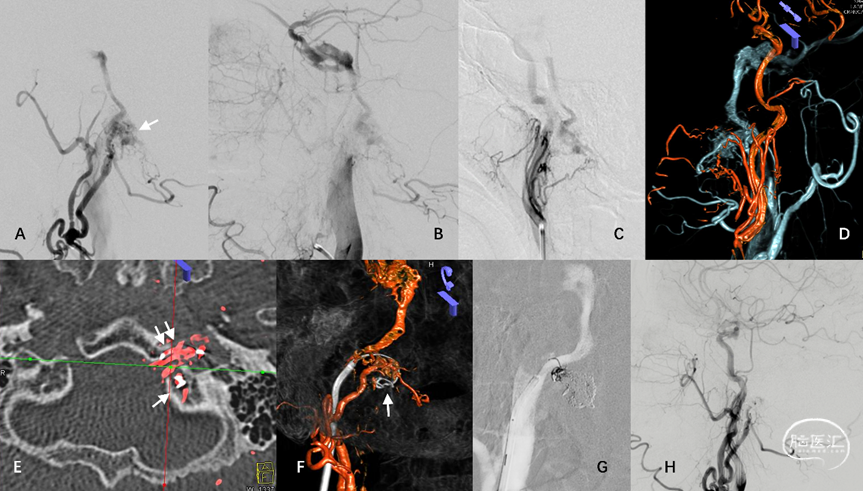

3.板障-导静脉型硬脑膜动静脉瘘(diploic-emissary vein type DAVF, DEV-DAVF),即动-静脉移行起自骨内的板障静脉或穿骨的导静脉,向静脉窦或浅表静脉系统引流。影像学表现为骨内静脉结构早显,并早于静脉窦显影(图4)。

图4. 骨内静脉系统与板障-导静脉型DAVF。板障-导静脉型DAVF,骨内的初级静脉(A白箭)汇聚至板障静脉SP(B双白箭),经蝶顶窦-海绵窦向眼静脉侧裂浅、深静脉逆流(C)。

DAVF的血管构筑包括本中心提出的新分型、Cognard分型、部位、偏侧性、初级静脉结构的位置,伴有静脉流出道梗阻以及与邻近梗阻静脉窦的位置关系。DAVF的偏侧分为左侧、右侧及中线病变。DAVF的位置包括:侧窦区、天幕区(包括天幕缘及天幕内侧)、上矢状窦区、前颅底、窦汇区、髁前区、大脑镰及其他少见部位。DAVF的初级静脉结构包括:(1)硬膜血管汇集区(Shunted pouch, SP);(2)桥静脉硬膜内段;(3)骨内静脉湖。以上结构通过常规血管造影及三维融合成像进行评估,对结构定位不确定时,参考高分辨磁共振(magnetic resonance imaging, MRI)、双容积融合成像辅助定位。以下为不同部位不同类型的硬脑膜动静脉瘘DSA特点。

图19. 髁前区DAVF典型血管构筑。A-C:枕动脉、咽升动脉供血分支向颈静脉结节静脉丛(JTVC)(白箭)汇集,经岩下窦向海绵窦、侧裂浅静脉逆流。D:ECA主干与咽升动脉双容积融合成像。E:位于骨内的JTVC(白箭)是髁前区板障-导静脉型DAVF的初级静脉结构。F:术中利用微导丝与静脉双容积融合成像定位。G-H:TVE闭塞JTVC及髁前静脉,治愈性栓塞DAVF同时保护岩下窦